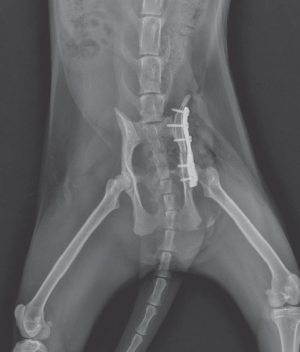

3D printing을 통해 수술 전 플레이트 성형을 미리 실시하여 수술 시간을 최소화하며 플레이트 적용을 원칙으로 하되 부위에 따라 외고정 장치를 사용하기도 합니다.